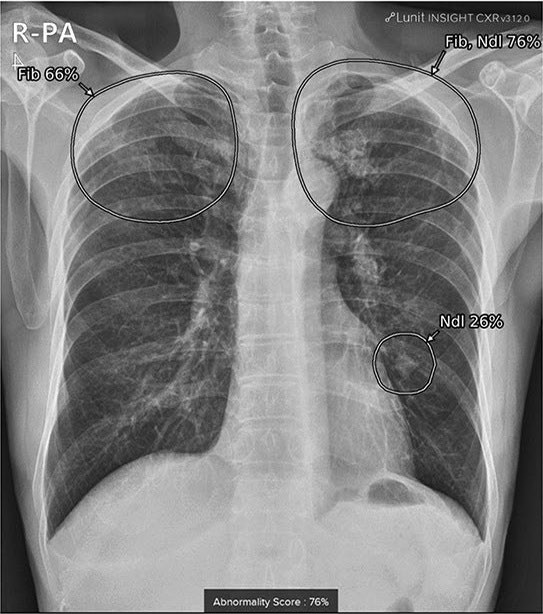

from www.mdpi.com

Sensors Free FullText Weak Localization of Radiographic

Sensors Free FullText Weak Localization of Radiographic What Are Nodules On Chest X-Ray Lung nodules often are discovered. Lung nodules are commonly found after a patient undergoes. The phrase ‘lung nodule’ describes a small, denser area of the lung which appears as a round spot on the image. A lung nodule is a small mass of dense tissue on the lung. They're typically smaller than 3 centimeters in diameter. Nodules are areas that. What Are Nodules On Chest X-Ray.